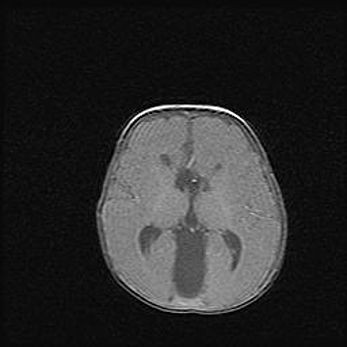

Аномалия Денди-Уокера. Признаки гипоплазии мозолистого тела.

Возраст: 5 месяцев 3 дня

Вес: 5550 г

Пол: мужской

Окружность головы: 39 см

Срок гестации: 40 недель

Аномалия Денди-Уокера – это порок развития головного мозга, для которого характерна триада симптомов: гипотрофия или аплазия червя мозжечка и/или полушарий мозжечка, расширение четвёртого желудочка с формированием ликворной кисты задней черепной ямки, гипертензионная гидроцефалия различной степени.

Гипоплазия мозолистого тела относится к дефектам внутриутробного этапа развития мозговой ткани, возникающим в процессе закладки структур головного мозга, что происходит на начальных этапах развития эмбриона.